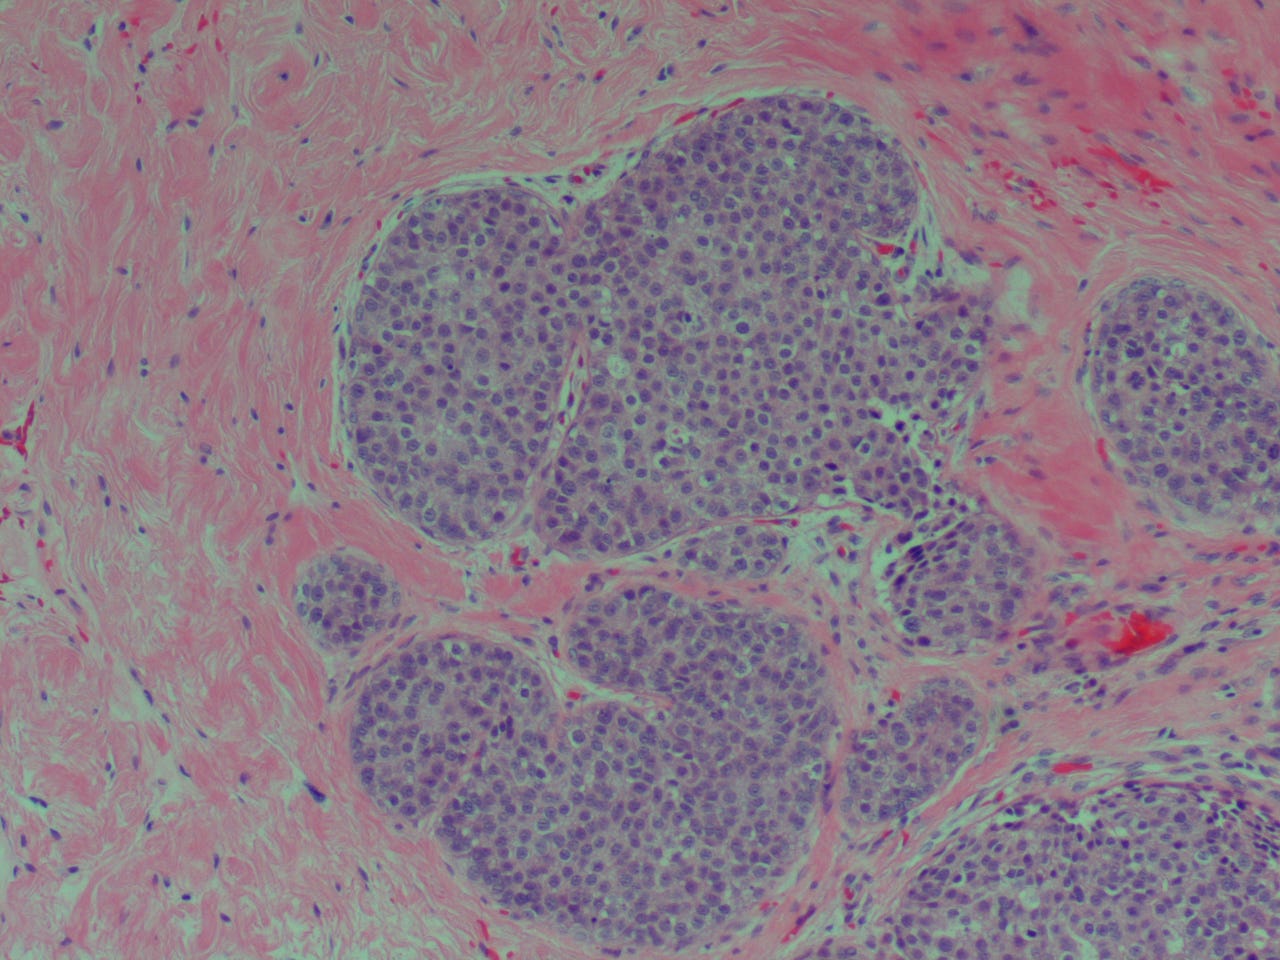

Переходноклеточный рак простаты - фото презентация